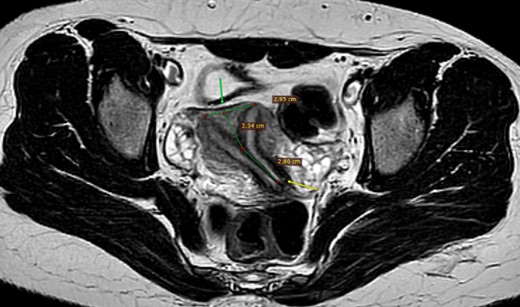

The patient underwent a comprehensive diagnostic workup. A hormonal assay of the patient showed that follicle-stimulating hormone, luteinizing hormone and thyroid-stimulating hormone were all within the normal range, except for prolactin level, which was elevated (64.72 ng/ml reference range 4.79–23.3). In addition, pelvic and transvaginal ultrasounds were performed, but they were inconclusive. Pelvic magnetic resonance imaging (MRI) revealed a uterus that was normal in size, with two uterine cavities separated by a septum of low T2 signal, extending into the endocervical canal (Fig. 1). The surface of the fundus was convex in shape with an acute angle between uterine cavities, which was about 60°. A thin regular endometrium about 7 mm in each cavity was seen. Hysteroscopy showed a complete vaginal septum, cervical septum and a septum inside the uterus, reaching the fundus and separating the uterus into two separate cavities. A normal outer wall of the uterus was observed during laparoscopy of the patient.

MRI pelvis, axial T2, complete separate uterine cavity (complete septate uterus), two cervices openings (below arrow), no fundal cleft, inter-cornual distance = 29.5 mm (above arrow), the upper 23.5 mm of the septum is composed of myometrium, while the distal 28 mm is composed of fibrous tissue.